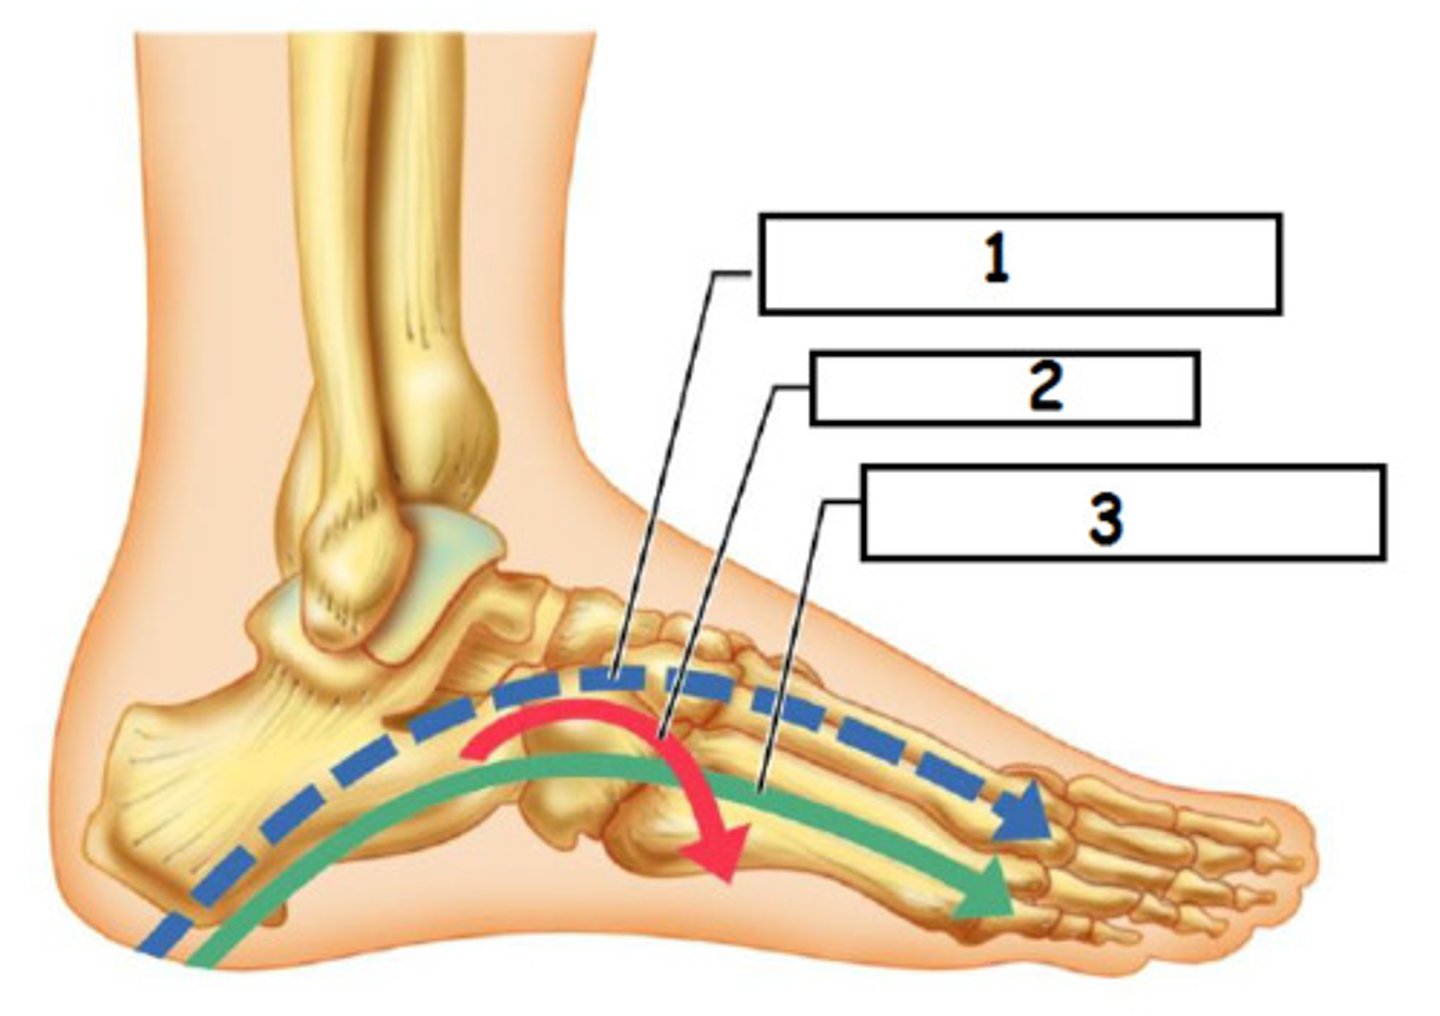

talus

navicular

cuneiforms

cuboid

transverse arch

longitudinal arch